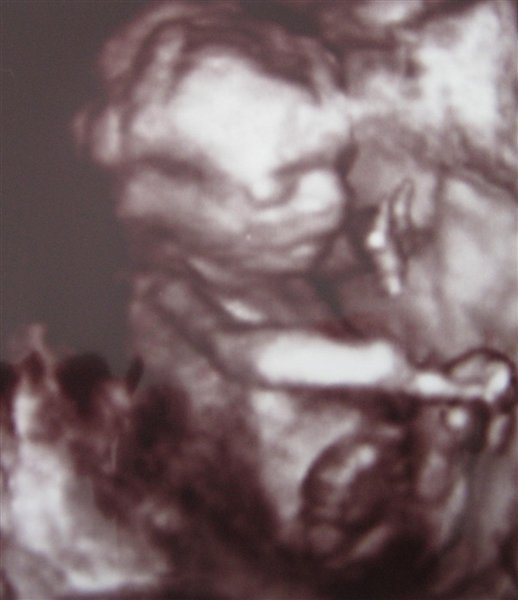

Her er Stellas nye Lillebror 27+3: